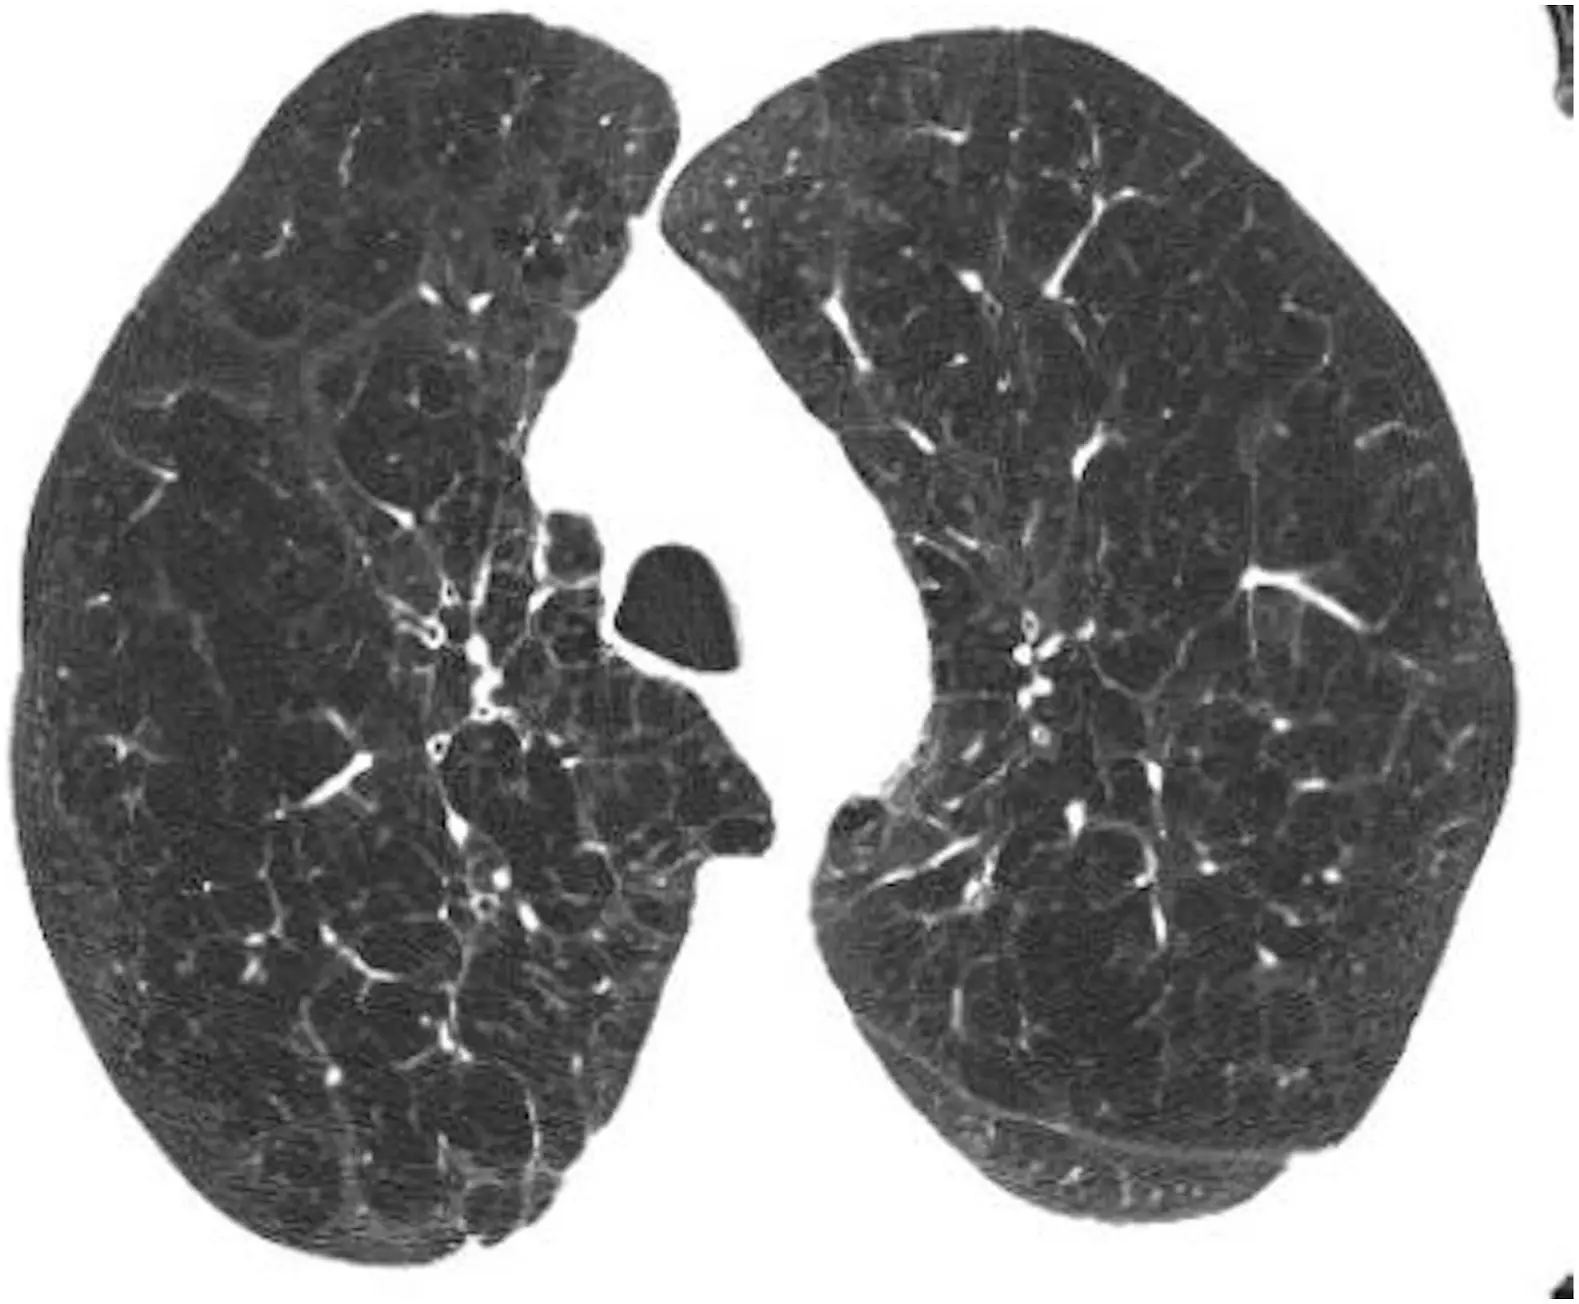

- Emphysema

- Bronchiectasis

- Interstitial lung disease (other than pulmonary fibrosis)

- Ground-glass opacification

- Pulmonary fibrosis

- Pulmonary nodules

Emphysema